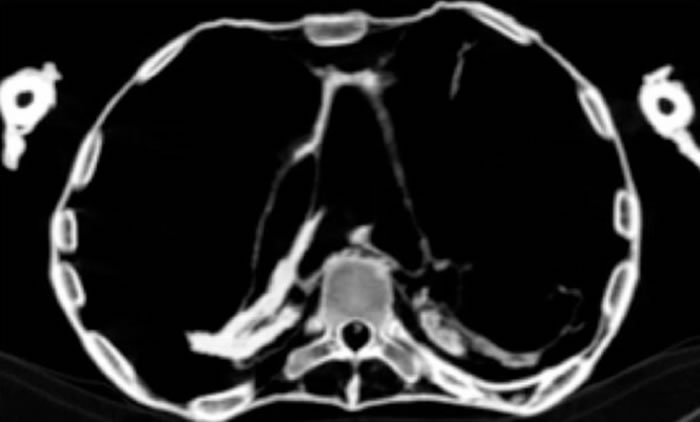

(报道)据ETtoday(吴美依/编译):埃及乐蜀(Luxor)于1881年发现的代尔埃尔巴哈里(Deir El-Bahari)皇家墓穴中,有一具木乃伊张大嘴巴、双腿弯曲交叉,因死状凄惨而被命名「尖叫女人木乃伊」。知名埃及古物学家哈瓦斯(Zahi Hawass)与开罗大学放射学教授萨利姆(Sahar Saleem)透过电脑断层扫描研究发现,这名埃及公主3000年前因心脏病发骤逝,终于解开多年谜团。

根据埃及《金字塔报》(Ahram Online),哈瓦斯表示,木乃伊死前看似非常恐惧、痛苦,张大嘴巴仿佛在尖叫,经电脑断层扫描研究与分析后发现,这名60多岁的女性冠状动脉出现严重动脉粥样硬化(Atherosclerosis),影响许多血管,导致心脏病发而突然死亡,但遗体获得良好防腐处理。